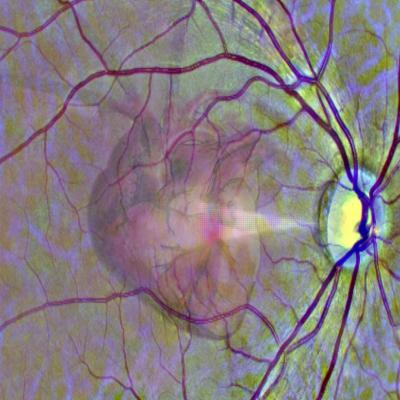

Image of a heart superimposed over a retinal image

A graphic representation of the idea of using a scan of the eye to get a window into heart health. Credit: University of Leeds.